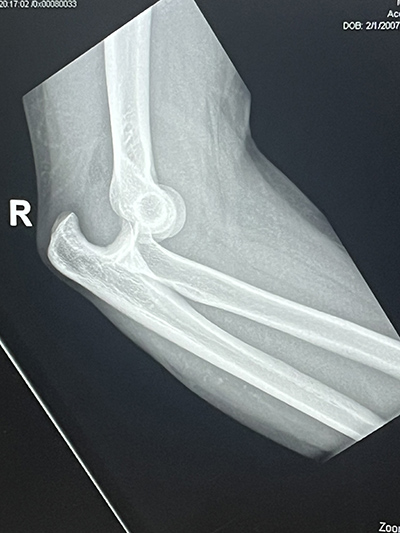

The first game of senior year was supposed to be one of celebration and promise for Logan Decker. Instead, it became a moment of shock. On his very first defensive play, Logan was tackled hard. As players piled on, his elbow popped out of place. Heading to the Emergency Department that night, Logan feared the worst, that his high school football season, and possibly his future college opportunities, were over.